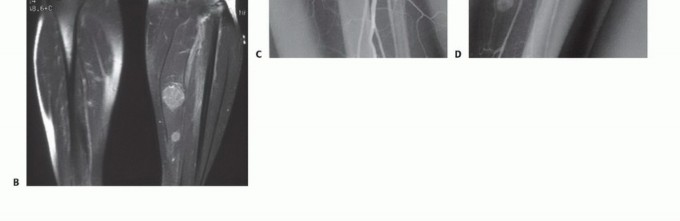

When performing a CNB, image guidance (ultrasound for superficial soft tissues or CT for deep/intraosseous lesions) is highly recommended to ensure the most biologically active portion of the tumor is sampled, deliberately avoiding areas of central necrosis.

2. Trajectory: The needle trajectory must traverse the absolute minimum amount of normal tissue necessary. It must not cross multiple anatomic compartments, joint spaces, or contaminate major neurovascular bundles.

3. Sampling: A coaxial needle system (e.g., 11-gauge introducer with a 13-gauge cutting needle) is preferred. The outer cannula remains in place, protecting the tract from seeding, while the inner cutting needle is deployed multiple times to obtain several cylindrical cores of tissue.

4. Tract Tattooing: The entry site is often marked with a small dot of India ink or a localizing suture to ensure the exact tract is identified and excised during definitive surgery.